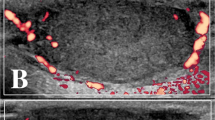

Tumour perfusion changes were also measured by Patent blue staining of the tumours with similar vascular effects as observed with other methods of measurement (Figure 6). An immediate reduction was observed in tumour perfusion after application of electric pulses and electrochemotherapy with reduction of tumour perfusion to 10% of the value in control tumours. Approximately 0.5 h later, the tumours started to reperfuse in both groups; in the tumours treated by electrochemotherapy, the reperfusion levelled at ∼1 h after the treatment and stayed at ∼20% up to 48 h after the treatment, whereas the tumours treated with application of electric pulses continued to reperfuse and reached normal values between 24 and 48 h.

Patent blue (Byk Gulden, Krenzlingen, Switzerland) was used to estimate tumour perfusion. Patent blue (1.25%) diluted in 0.2 ml 0.9% NaCl was injected at different time points after treatment into the tail vein of animals with tumours from the control, electric pulses, BLM and electrochemotherapy groups. After the dye was distributed evenly through the tissue (1 min), animals were killed and the tumours carefully excised. The excised tumours were removed from the skin, cut in half along their largest diameter and photographed. The images were evaluated using Image J software. The stained area of tumour cross-section was used as an indicator of tumour perfusion. In the study comparing Patent blue staining and the pharmacological method measuring the relative tumour blood flow, a good correlation (r=0.962) was found between both methods (Sersa et al, 1999a, 1999b).